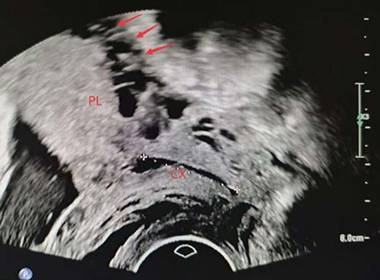

Ultrasound (US) and magnetic resonance imaging (MRI) have shown high diagnostic performance in the detection of PAS[17-19]. Ultrasound serves as the primary diagnostic tool for PAS; however, current clinical sonographic criteria are primarily validated for anterior PAS cases complicated by placenta previa. When the placenta invades the posterior uterine wall, the diagnostic accuracy of prenatal ultrasound in detecting characteristic signs remains uncertain[17, 18, 20]. Dellapiana et al. reported that the application of standard sonographic criteria results in a low antenatal detection rate for posterior PAS[21]. For optimal ultrasound diagnosis of posterior PAS, the recommended gestational window for initial screening is between 25 and 28 weeks. This timing is advantageous because: the uterine wall and placental architecture are more clearly visualized at this stage, the amniotic fluid-to-fetal size ratio is more favorable, and the posterior implantation site becomes more accessible for evaluation[22]. The ultrasound markers of PAS include: (1) Loss or irregularity of the hypoechoic area between the uterus and placenta, the 'retroplacental clear zone' (Figure 1), (2) Myometrial thickness <1mm, (3)placental lacunae with high velocity flow (>15cm/s) (Figure 2), (4)Thinning or interruption of the uterine serosa-bladder wall interface, (5) Placental bulge, (6) Exophytic mass,(7) Subplacental and/or uterovesical hypervascularity, (8) Loss of vascular arch parallel to the basal plate and irregular intraplacental vascularization (Figure 3)[3, 23]. After excluding the two bladder line-dependent criteria, the following four key sonographic features were consistently observed in the posterior placental region: loss or irregularity of the hypoechoic area between the uterus and placenta, myometrial thickness <1mm, placental lacunae with high velocity flow (>15cm/s), and Loss of vascular arch parallel to the basal plate and irregular intraplacental vascularization[22]. Many authors have adopted a two-criteria system in their articles: PAS is diagnosed when there are two or more ultrasonic signs present[22, 24]. The two-criteria system has a high sensitivity (60.0%), specificity (98.9%), and positive predictive value (85.7%). Moreover, when using a single criterion or the optimal criterion, there is no improvement in the maternal outcomes of true positive and false negative cases, which confirms the reliability of the two-criteria system[22]. A retrospective study has found that the sensitivity of ultrasound in detecting anterior PAS is as high as 81 - 93%[18]. Other studies have also validated this discrepancy. The ADoPAD (Antenatal Diagnosis of Placental Attachment Disorders) Study Group reported that prenatal ultrasound detected 92% of all anterior PAS cases, which was significantly higher than the 62% detection rate for posterior PAS[11]. The detection rates of PAS in anterior and posterior placentas were reported by Pilloni et al. as 89.7% and 50% respectively, under the application of the two - criteria system[24]. However, in a recent study, after excluding patients with placenta previa, only 30% of posterior placenta PAS cases were diagnosed through prenatal ultrasound screening. This suggests that compared with anterior PAS, ultrasound examination has lower sensitivity for posterior PAS[21]. An independent evaluation of the sensitivity of individual ultrasound signs for pathologically confirmed posterior and anterior PAS was conducted. The sensitivities of retroplacental lacunae, vascular congestion, myometrial thinning, and absence of hypoechoic areas in detecting posterior wall PAS ranged from 24% to 42%. However, multiple studies have demonstrated that the absence/irregularity of the retroplacental clear zone shows the highest sensitivity and negative predictive value for posterior placenta accreta - comparable to or even exceeding that of the dual-criteria system. These findings confirm the diagnostic importance of this specific criterion for posterior placenta accreta, while other criteria exhibit significantly lower sensitivities compared to the dual-criteria system[22, 24]. This divergence primarily stems from hemodynamic differences, as the posterior uterine wall's lower segment demonstrates greater vascularity compared to the anterior wall. Sonographically, the retroplacental clear zone shows better echogenic contrast with posterior placental positioning than with anterior implantation. Consequently, when placental invasion disrupts the retroplacental clear zone's integrity, sonographic abnormalities become more detectable on the posterior uterine wall. This diagnostic advantage is most evident between 26 and 28 weeks of gestation[24]. In summary, ultrasound demonstrates suboptimal sensitivity for detecting posterior PAS. As the first-line imaging modality, its diagnostic performance is limited by three key factors: (1) operator-dependent variability, (2) reduced efficacy in obese patients, and (3) poor detection of posterior placental invasion. These limitations collectively compromise both the accuracy and clinical utility of ultrasound for posterior PAS diagnosis. Furthermore, current research on posterior PAS remains constrained by small sample sizes, highlighting the need for larger-scale studies to validate existing findings[22].

Figure 1

Loss or irregularity of the hypoechoic area between the uterus and posterior placenta (arrow). PL, placenta. CX, cervix